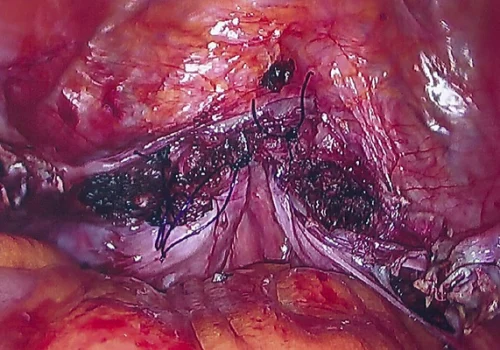

Procedure

She subsequently underwent Total Laparoscopic Hysterectomy and removal of both Fallopian Tubes and Ovaries. The uterus weighed 670g.